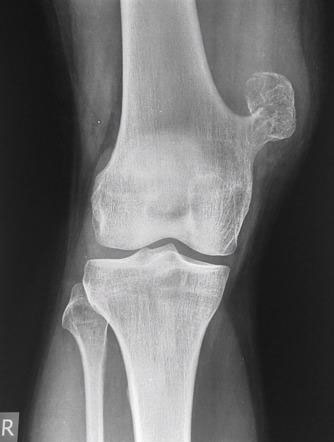

Bone tumors are rare lesions. A large part of these tumors are benign lesions, and they often occur by chance during radiological examinations for another reason. As a complaint, they usually show swelling and pain. Rarely, it is diagnosed after causing a fracture in the place where it was. Osteoid osteoma, osteochondroma (exostosis), enchondroma, non-ossifying fibroma, eosinophilic granuloma, simple bone cyst, fibrous dysplasia and intraosseous lipoma/ganglion are the most common lesions of benign tumors.